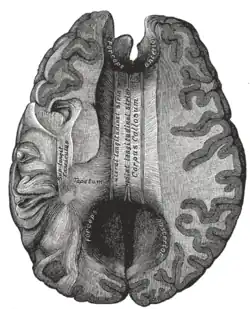

![]() Sagittal section of brain, front part to the left. The corpus callosum can be seen in the center, in light gray | |

The corpus callosum (Latin for "tough body"), also callosal commissure, is a wide, thick nerve tract, consisting of a flat bundle of commissural fibers, beneath the cerebral cortex in the brain. The corpus callosum is only found in placental mammals.[1] It spans part of the longitudinal fissure, connecting the left and right cerebral hemispheres, enabling communication between them. It is the largest white matter structure in the human brain, about 10 in (250 mm) in length and consisting of 200–300 million axonal projections.[2][3]

The corpus callosum forms the floor of the longitudinal fissure that separates the two cerebral hemispheres. Part of the corpus callosum forms the roof of the lateral ventricles.[5]

The corpus callosum has four main parts – individual nerve tracts that connect different parts of the hemispheres. These are the rostrum, the genu, the trunk or body, and the splenium.[4] A narrowed part between the trunk and the splenium is known as the isthmus. Fibres from the trunk and the splenium known together as the tapetum form the roof of each lateral ventricle.[6]

The callosal sulcus separates the corpus callosum from the cingulate gyrus.